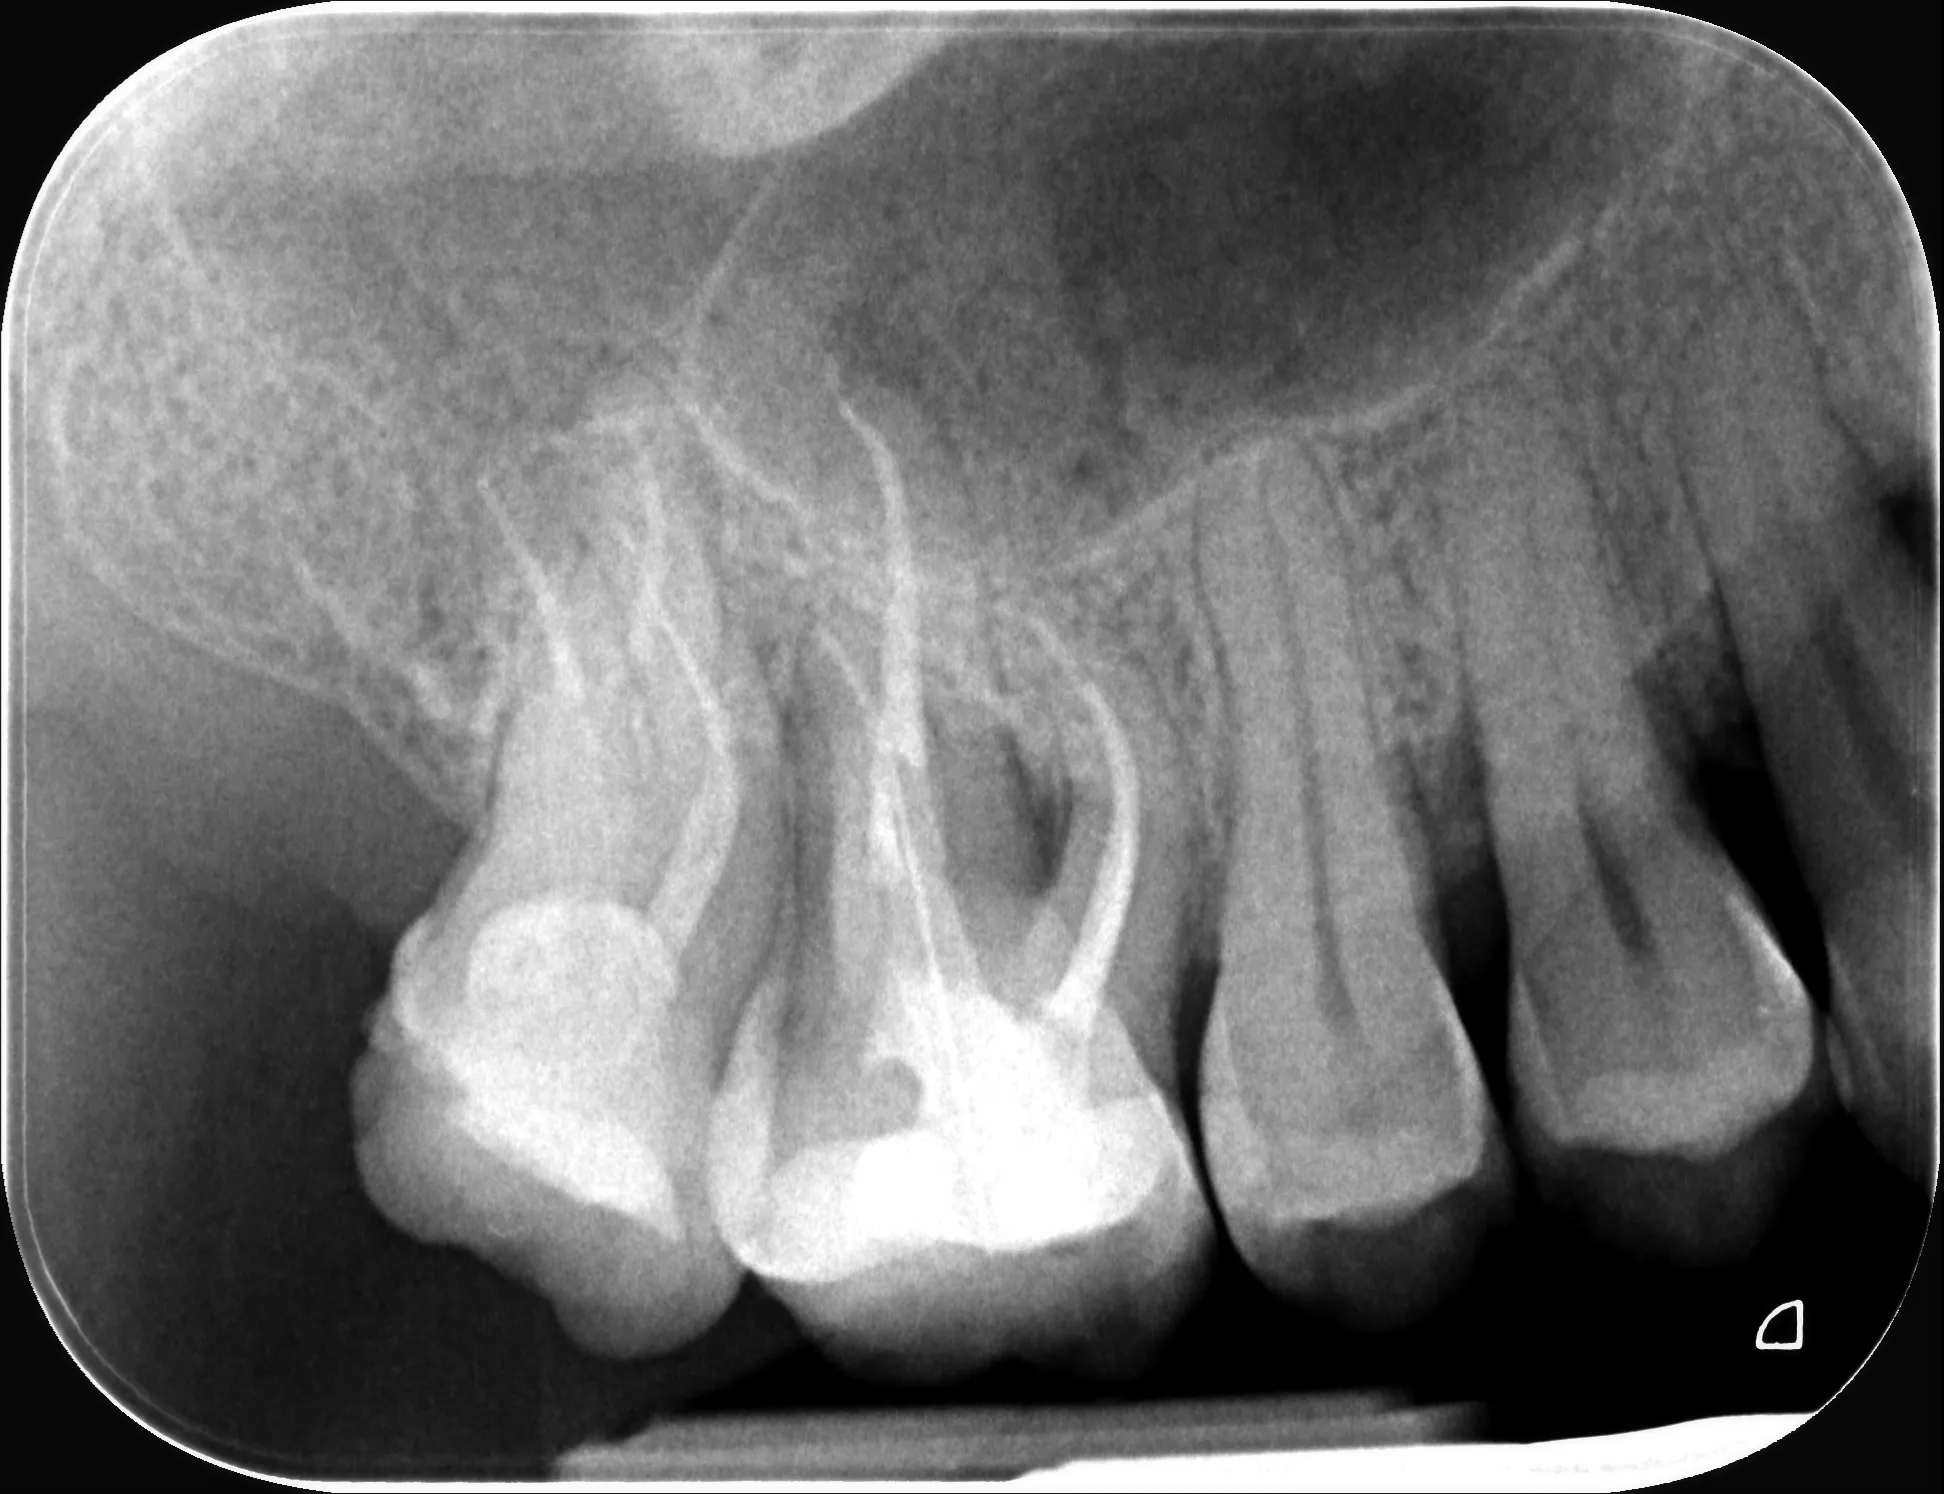

1 – Radiografie inițială